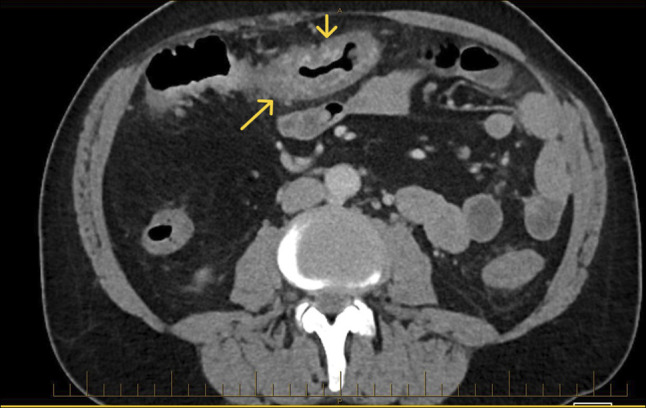

由于特发性结肠静脉曲张(ICV)引起的下消化道出血是非常罕见的。我们报告一位66岁男性复发性尿血,但没有肝脏疾病或门静脉高压症病史。结肠镜检查显示整个结肠有广泛的静脉曲张。没有生化或放射学证据表明肝硬化或门静脉高压症。ICV的潜在病因尚不清楚,在没有标准化治疗方案的情况下,这种疾病的管理具有挑战性。非选择性β受体阻滞剂可以考虑,尽管未知的ICV病理生理和他们的作用在这个临床实体。在我们的病例中,成功的管理包括立即内窥镜治疗和卡维地洛的二级预防。

Lower gastrointestinal bleeding due to idiopathic colonic varices (ICV) is very rare. We present a 66-year-old man with recurrent hematochezia but without history of liver disease or portal hypertension. Colonoscopy revealed extensive varices throughout the colon. There was no biochemical or radiological evidence of cirrhosis or portal hypertension. The underlying etiology of ICV is unknown, and management of this condition is challenging without standardized treatment protocols. Nonselective beta-blockers could be considered despite the unknown ICV pathophysiology and their effect in this clinical entity. The successful management in our case included immediate endoscopic treatment and secondary prophylaxis with carvedilol.